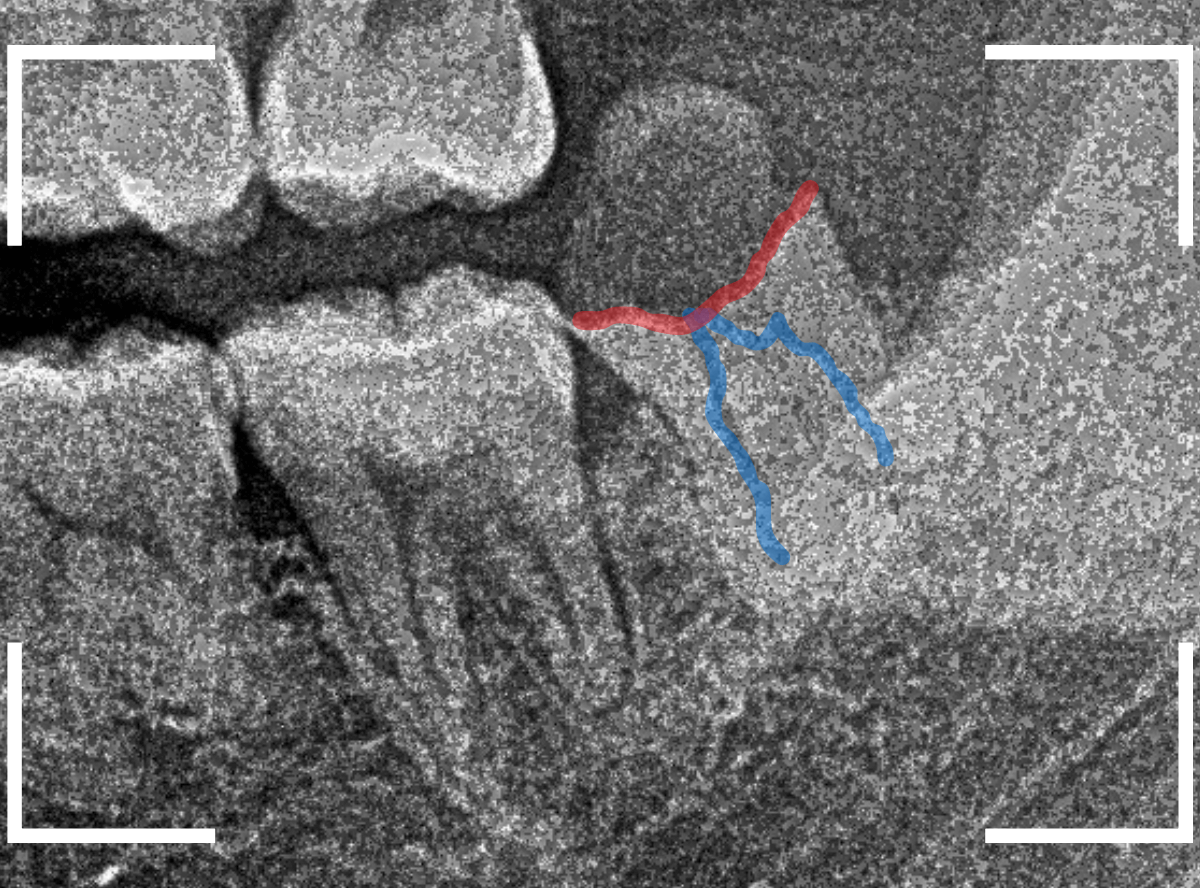

ここでは、比較的簡単なおやしらずの抜歯の例を中心にご紹介します。

このようなおやしらず、あなたはありませんか?